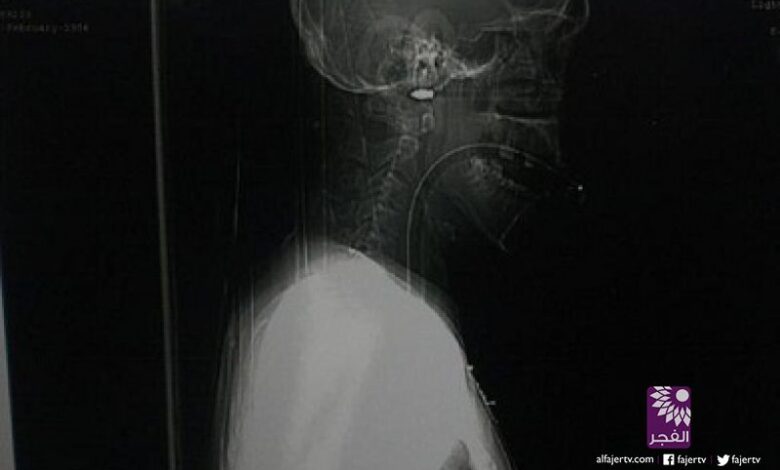

ونقل الشاب سريعاً إلى المستشفى، وأجرى له الجراحون جراحة سريعة نزعوا السهم منه، ولكن ظل رأسه، الذي يبلغ طوله ثماني بوصات، داخل جمجمته ولم يتم استخراجها خوفاً على حياته.

وقالت إدارة المستشفى إن الشاب كان على وشك أن يفقد حياته، لو كان الرأس تحرك بضعة مليمترات فقط، حيث كان على بعد مليمتر واحد، من الشريان السباتي، ما كان سيجعله يفقد حياته أو تصيبه أعراض خطيرة مثل الشلل النصفي.